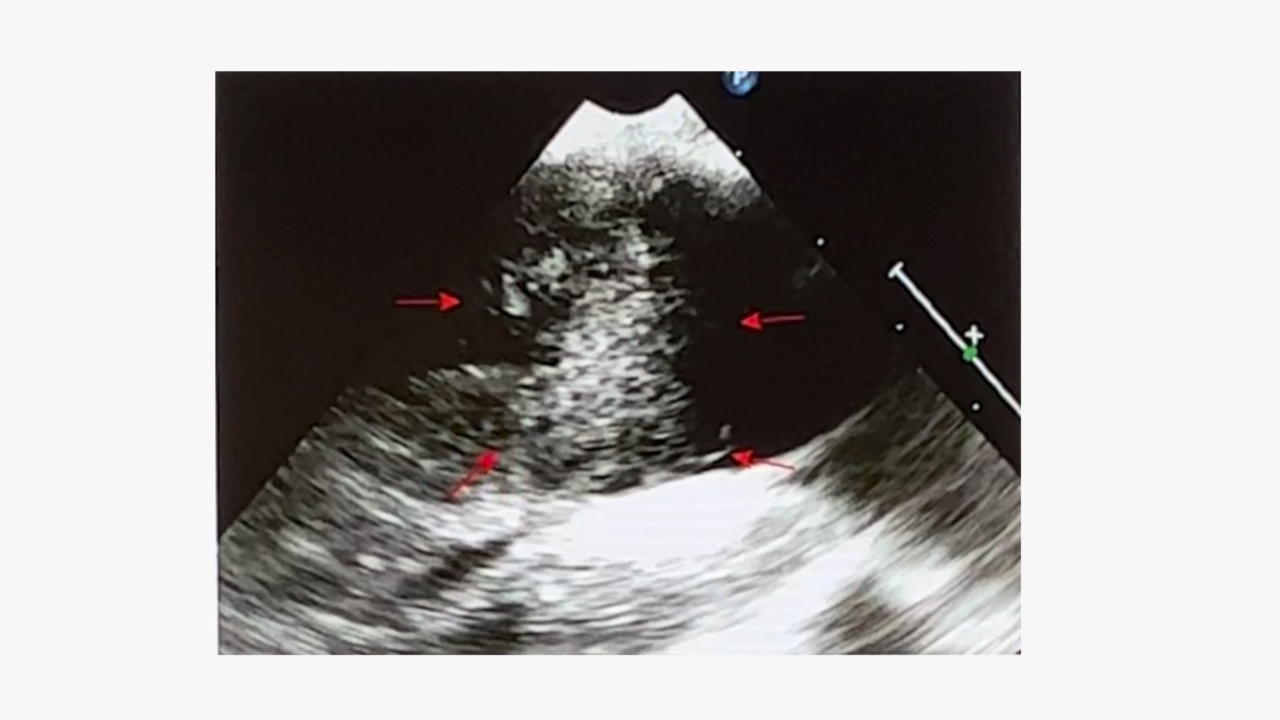

下腔静脉超声波检查:提示下腔静脉内实性结节,与血管壁无粘连。

MRI可显示左侧宫旁血管明显扩张,管腔内存在充盈缺损,有助于定位血管内病变。